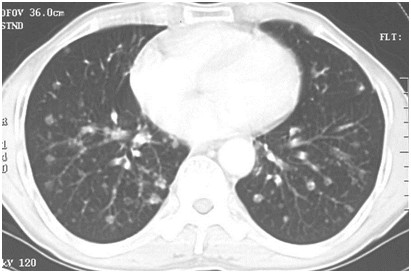

02卷-3.男性,55岁,结肠癌术后2年。(本题满分2.00分)

本题答案:D

题目解析:

【该题针对“ X线-肺癌 ”知识点进行考核】